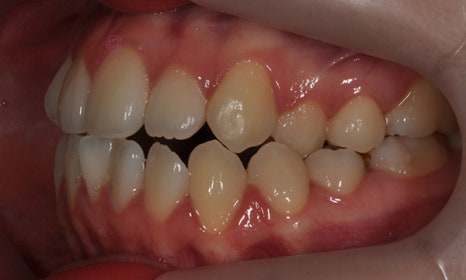

다음 케이스 역시 위 아래 중심선의 차이가 있어서 비대칭이 있어 보이는 케이스입니다. 중심선의 차이 뿐 아니라 앞니 및 어금니 부위에 거꾸로 물리는 반대교합이 관찰되고 있었습니다(원래는 위 치아가 아래 치아를 덮는 것이 정상적인 교합이나, 반대교합이란 위 치아가 아래 치아보다 더 안쪽으로 들어가서 물리는 교합을 말합니다).

2020.2

얼굴의 중심선과 위 치아의 중심선은 일치하여, 오른쪽 아래 작은 어금니를 발치하여 그 공간으로 아래 치열을 이동시켜줌으로써 중심선 및 교합을 개선하였습니다.